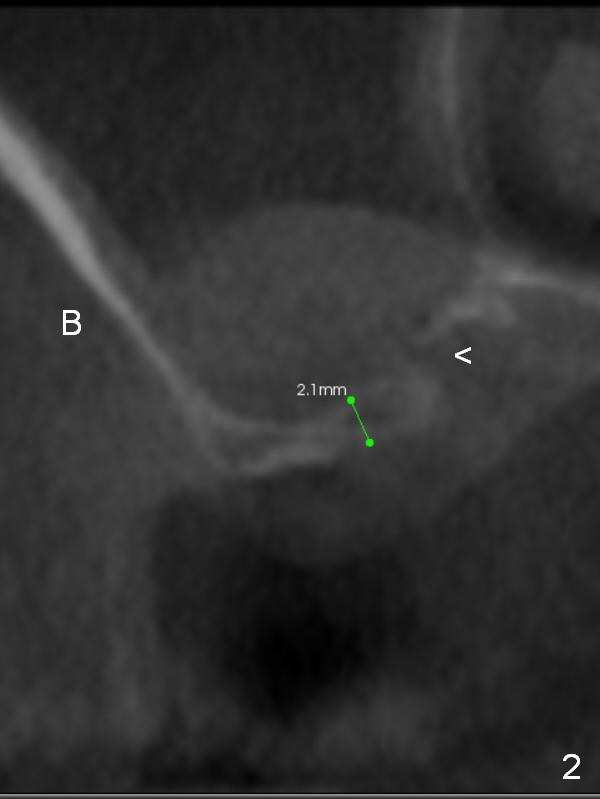

Implant in Thin Sinus Floor

A 48-year-old lady has severe bilateral sinus pneumotization, especially at the right 1st molar (Fig.1 CBCT). The sinus floor is 2 mm thick (Fig.2 coronal section). Sinus lift may require lateral window approach (Fig.2 B (buccal). Implantation may be accomplished at the same time (Fig.1). * in Fig.1: mucocele; < in Fig.2: possible perforation. An implant will be placed at #31 later.